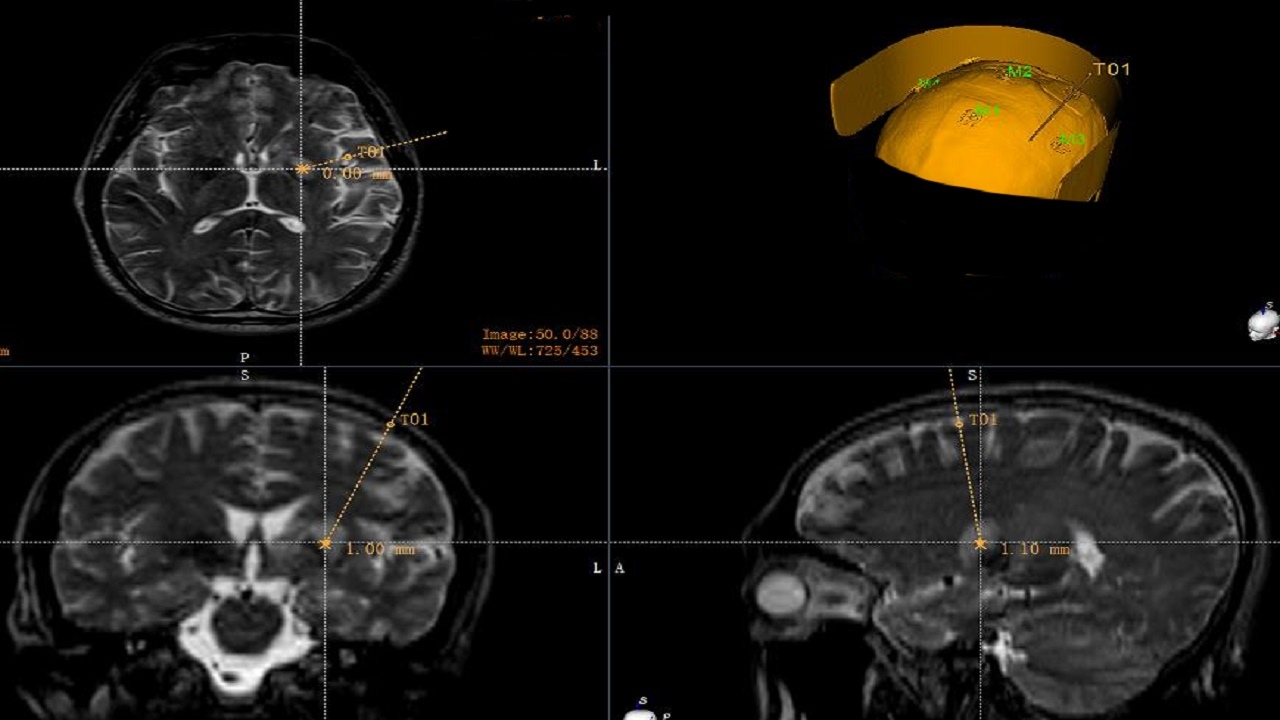

立体定向脑活检手术:手术路径计划

病理结果确诊为:淋巴细胞性PACNS